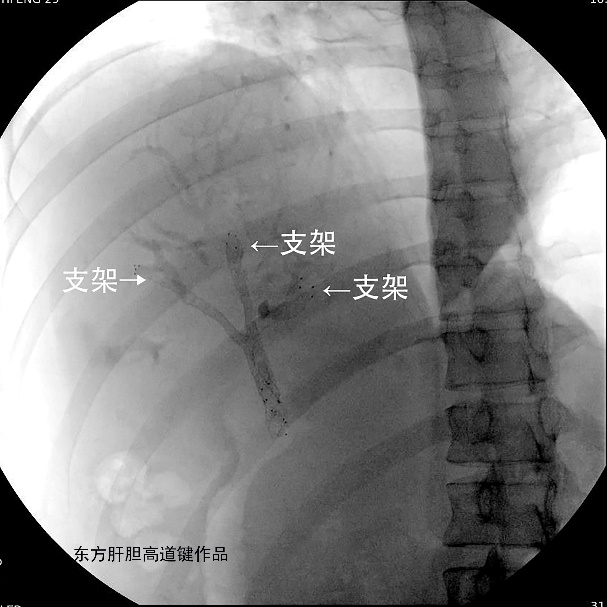

图L:三根金属支架定位良好。